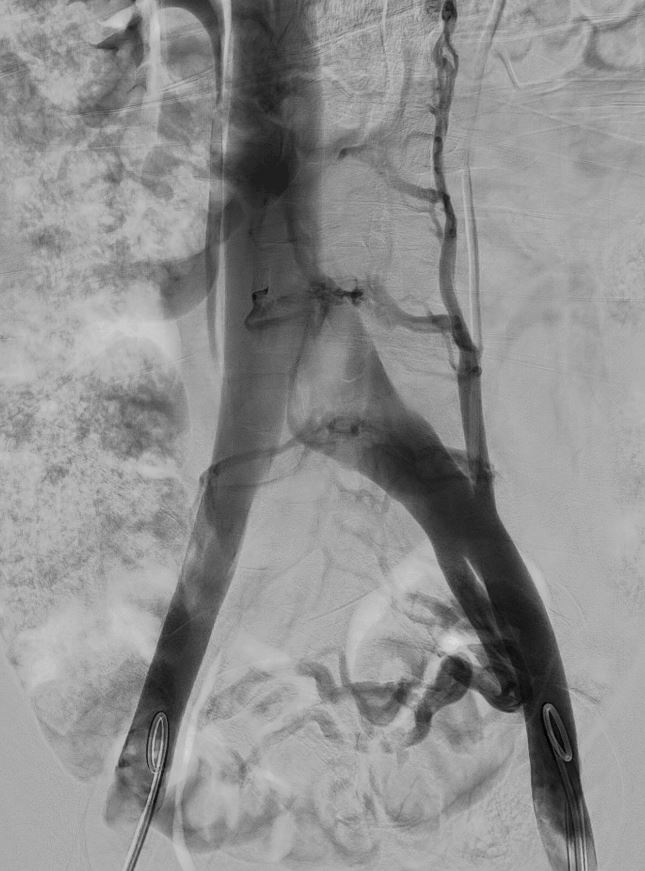

- Flebografía

Es una prueba diagnóstica mínimamente invasiva que nos aporta imágenes de gran calidad acerca de la morfología y el flujo de las venas, valorando las posibles lesiones. La flebografía pélvica o iliocavografía, permite medir gradientes de presión y realizar el tratamiento de embolización en el mismo acto.

Nuestro enfoque en el tratamiento de esta condición es la embolización de todas las venas pélvicas patológicas, lo que ha demostrado ser altamente efectivo para mejorar considerablemente la calidad de vida de las pacientes.Nuestro servicio de Angiología y Cirugía Vascular colabora estrechamente con la Unidad Posparto para brindar apoyo a las pacientes que experimentan síntomas de síndrome de congestión pélvica después de dar a luz a su bebé.

Adicionalmente, es importante destacar que estas varices pueden ser secundarias a síndromes compresivos como el Síndrome de Nutcracker (compresión de la vena renal izquierda) y el Síndrome de May-Thurner (compresión de la vena iliaca izquierda).

Para tratar afecciones venosas, utilizamos técnicas como la radiofrecuencia de varices en miembros inferiores, la embolización de varices pélvicas, el stenting de compresiones venosas y la fibrinólisis fármaco-mecánica para trombosis venosas. Estos procedimientos son altamente efectivos y ofrecen resultados notables para mejorar la salud venosa y la calidad de vida de nuestros pacientes.